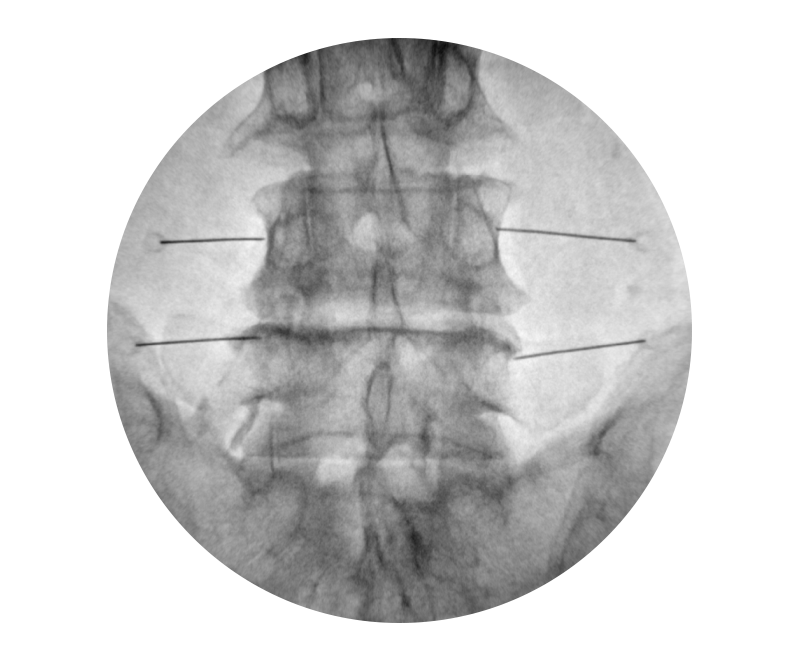

À̵¿½Ä X-ray ÃÔ¿µ ±â°è¸¦ ÀÌ¿ëÇÏ¿© ½Ã¼ú ºÎÀ§ÀÇ ÃÔ¿µÀ» ÅëÇØ ¹Ù´ÃÀ̳ª

ÁÖ»çÀÇ ¾à¹°À» ½Å°æºÐÀý ºÎÀ§¿¡ ÁÖÀÔÇÏ´Â ½Ã¼ú·Î Àϸí '½Å°æÂ÷´Ü¼ú'À̶ó ºÒ¸³´Ï´Ù.